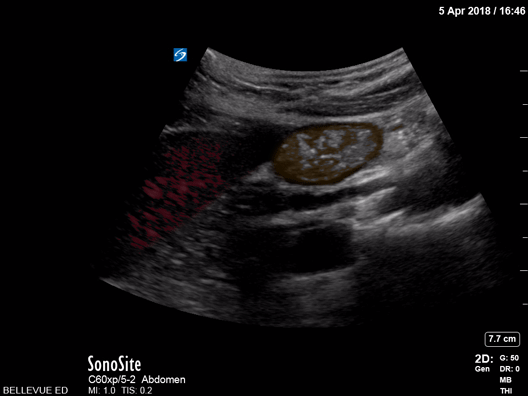

Duodenum and Liver Orange: Duodenum, Red: Liver Images: Dr. Lindsay Davis, Dr. Hannah Kopinski. Image Editing: Michael Amador and Dr. Matthew Riscinti